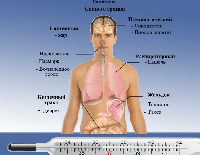

Магнитно-резонансная томография (МРТ):один из самых эффективных методов диагностики заболеваний